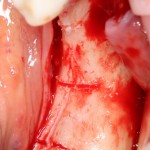

Остеопластика — всего одна операция.